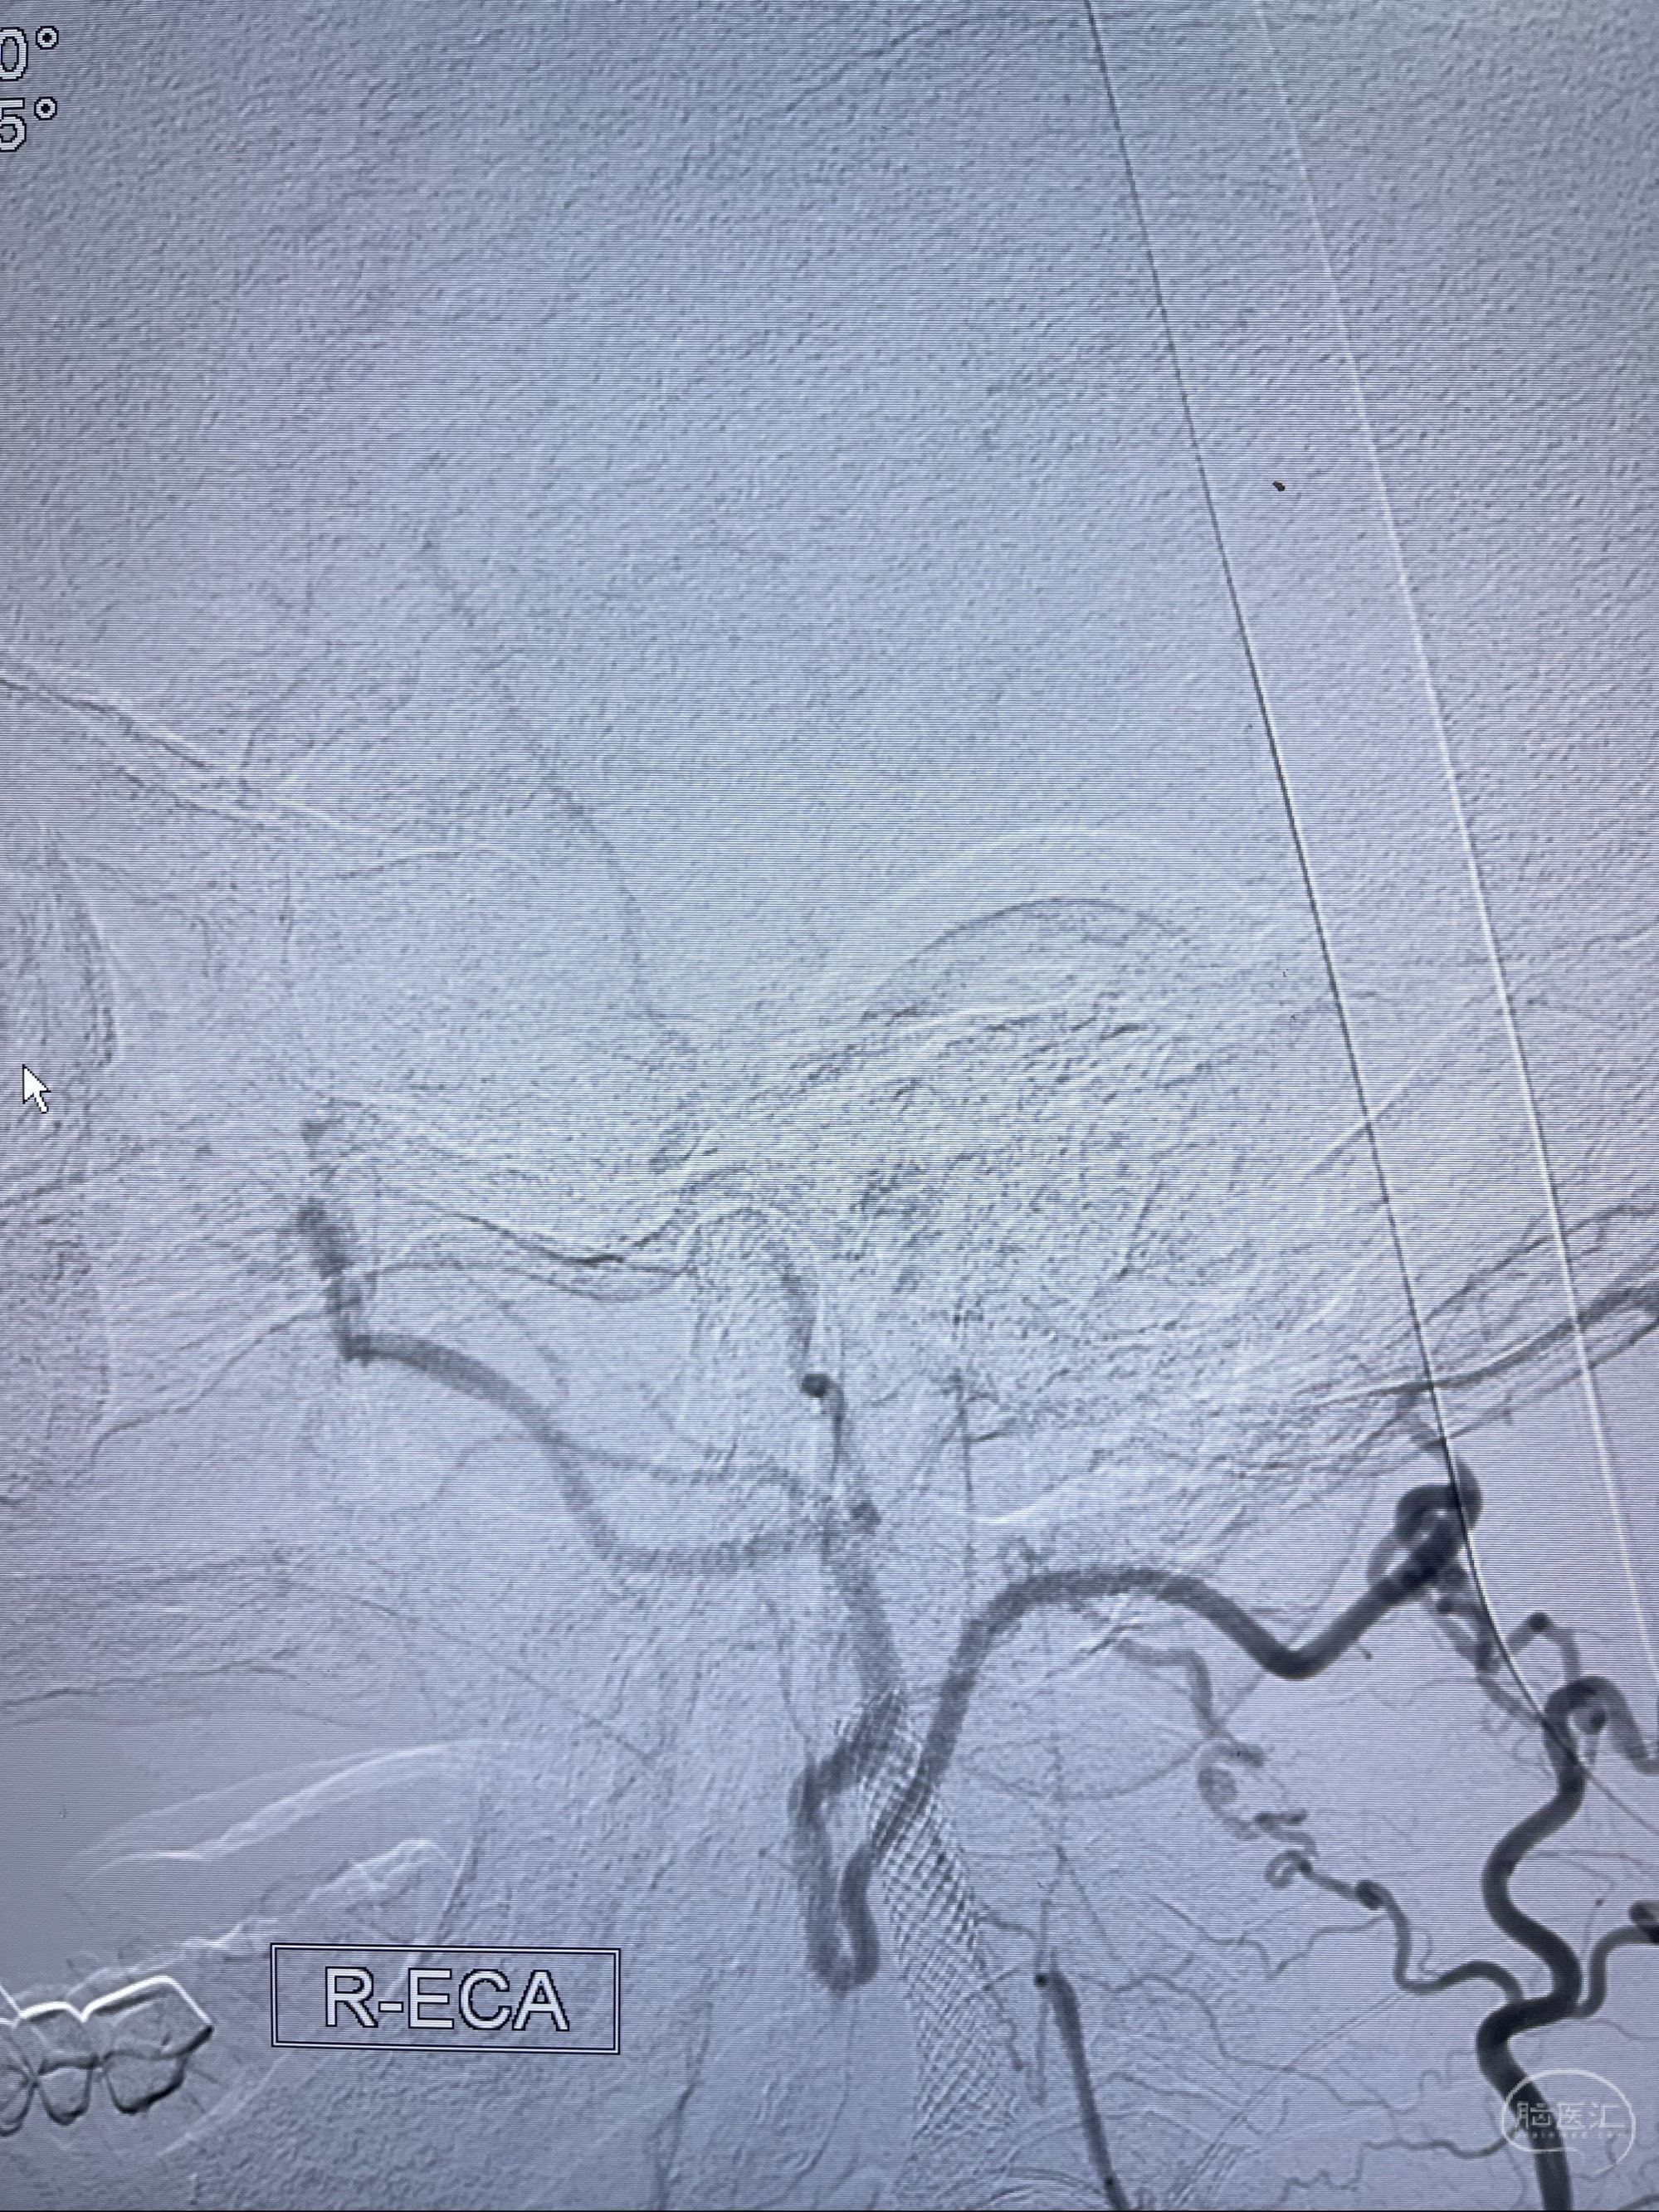

2023-07-10DSA:右侧颈内动脉岩骨段夹层伴中偏重度狭窄改变,左侧颈总动脉闭塞、右侧颈外动脉由右侧肋颈干甲颈干吻合代偿

箭头所示为颈内动脉岩骨段重度狭窄,结合MRI,考虑为肿瘤侵犯右侧颈内动脉

箭头以近至支架段管腔不规则狭窄

右侧椎动脉可见吻合代偿右侧颈外动脉